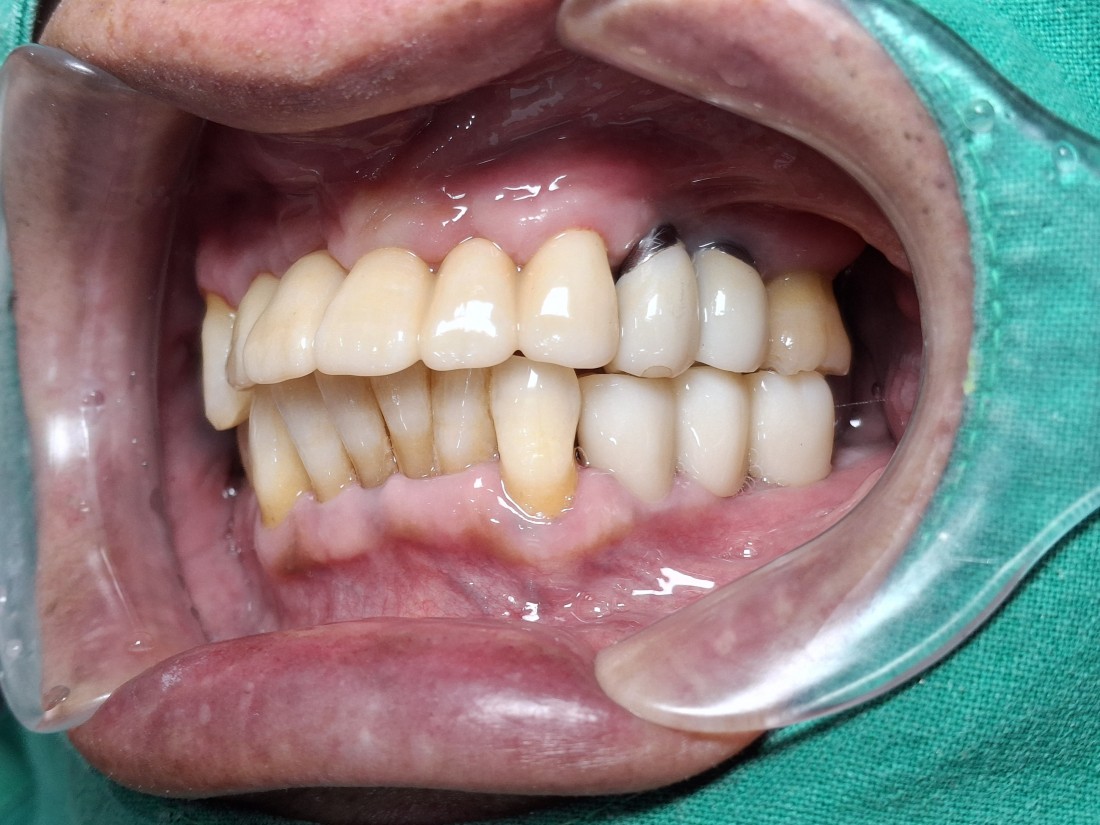

광주 앞니임플란트 치과에서

자연치아만큼 아름다운 앞니임플란트를

완성할 수 있는 비결에는

'핑크 포세린'을 이용하여

잇몸을 제작하기 때문에

더욱 자연스러운 아름다운 앞니를

연출할 수 있기 때문입니다.